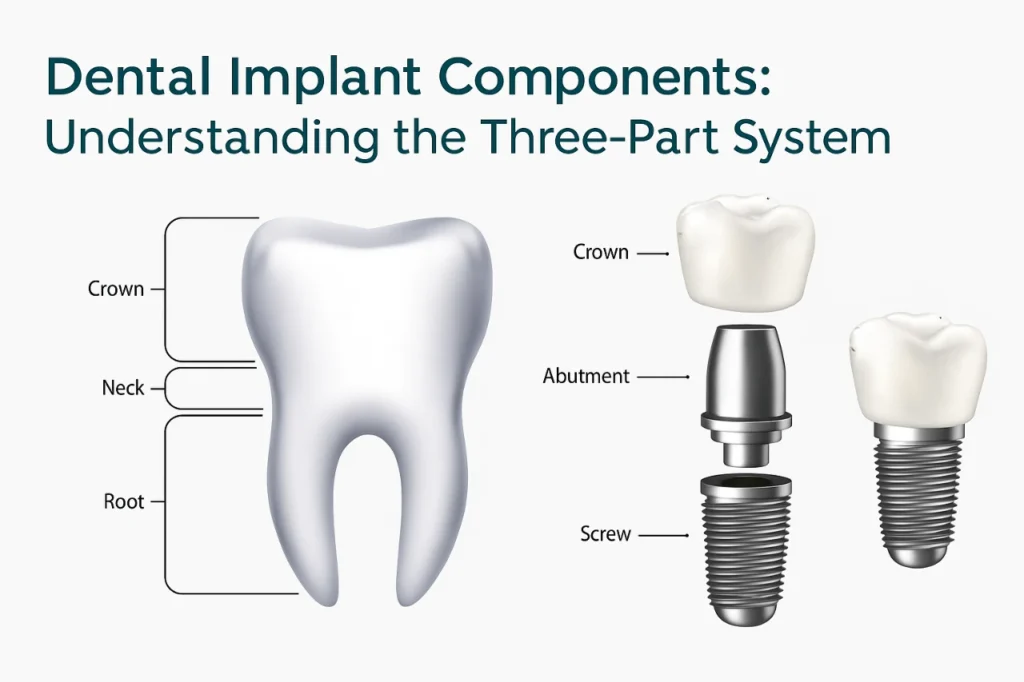

By serving as artificial tooth roots, implants deliver strength and stability that traditional options may not. With several treatment types available, implant care can be tailored to meet different needs, whether replacing a single tooth or restoring a full smile.

An untreated missing tooth may lead to tooth movement and uneven bite pressure over time. Single-tooth implants replace both the root and the visible portion of the tooth, providing a secure, independent solution.

Because the implant stands on its own, nearby teeth remain untouched. The result is a natural-looking replacement that restores chewing ability and helps maintain jawbone structure.

After implants are placed, restoration completes the process by attaching crowns, bridges, or dentures. Ongoing maintenance helps protect the implant and surrounding tissues.